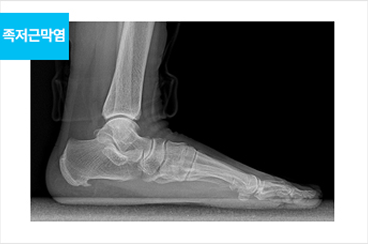

족저근막 유리술이란?

족저근막이 신경을 압박하는 주변 조직을 절개하고, 족저근막이 받는 부담을 낮춰 통증을 완화하는 수술입니다.

최소 절개로 흉터가 작고, 빠른 일상생활 복귀가 가능합니다.

발이 받는 부담이 줄어 들어 통증이 완화됩니다.

족저근막염

족저근막염 치료 전

족저근막염 치료 후

족저근막염이 생기는 원인

족저근막염 치료방법

바른마디 스토즈충격파가 해답입니다.

바른마디병원 스토즈 충격파 요법은 여러 근골격계 질환을 해결합니다. 석회화건염, 유착성 관절낭염(오십견), 테니스 엘보, 골프 엘보, 아킬레스건염 등에 특히 효과적입니다. 수술적인 치료 없이, 충격파 치료는 큰 통증 없이 염증이 발생한 부위에 바른마디병원 스토즈의 방사형(레디알) 충격파를 적용하여 작은 혈관들의 생성을 촉진하고, 손상된 조직이 더욱 튼튼하게 재생될 수 있도록 돕습니다.

단, 충격파 치료로도 호전되지 않는 만성 족저근막염의 경우, 관절내시경을 이용한 수술적 치료를 고려해야 합니다.